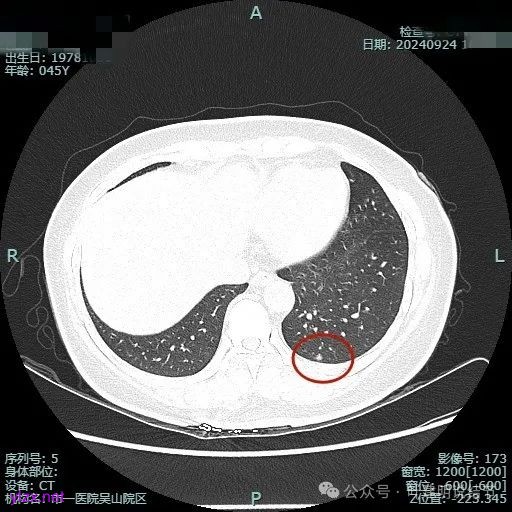

病灶3:

左下叶基底段微小结节,也是混合密度偏实性,瘤肺边界稍不清,与右侧的是类似形态的。